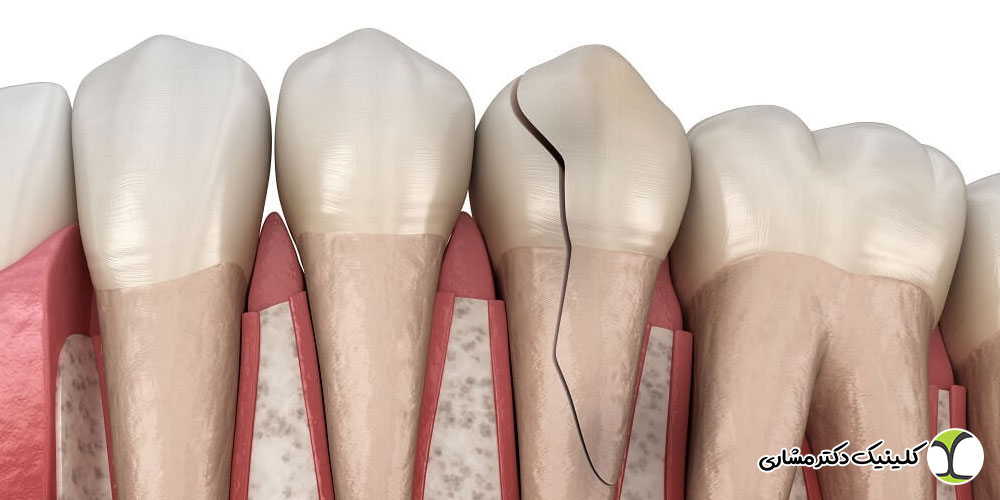

- پوسیدگی جدید یا شکستگی دندان

شکستگی ترمیم یا روکش تاج

ترمیم ناقص، پوسیده یا ترک خورده و همچنین شکستگی روکش تاج می تواند راه ورود باکتری ها به کانال ریشه را فراهم کند و باعث عفونت مجدد شود. در چنین شرایطی حتی درمان اولیه موفق هم ممکن است نیاز به تکرار پیدا کند.